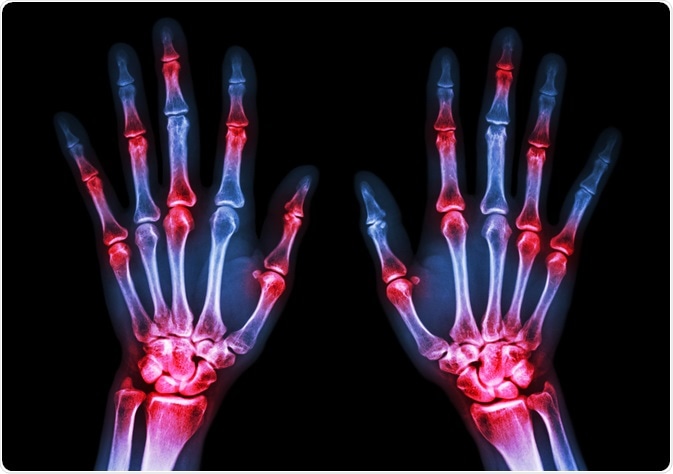

Rheumatoid arthritis (RA) is an autoimmune disorder that causes inflammation of the joints. RA is a chronic and progressive condition that causes debilitating effects on the patient. The condition is characterized by pain and stiff joints.

arthritisImage Credit: Puwadol Jaturawutthichai / Shutterstock.com

Another typical feature of this disorder is bone and joint destruction and the presence of autoantibodies in the serum and synovial fluid. Synovial fluid is the fluid that lubricates the synovial joints.